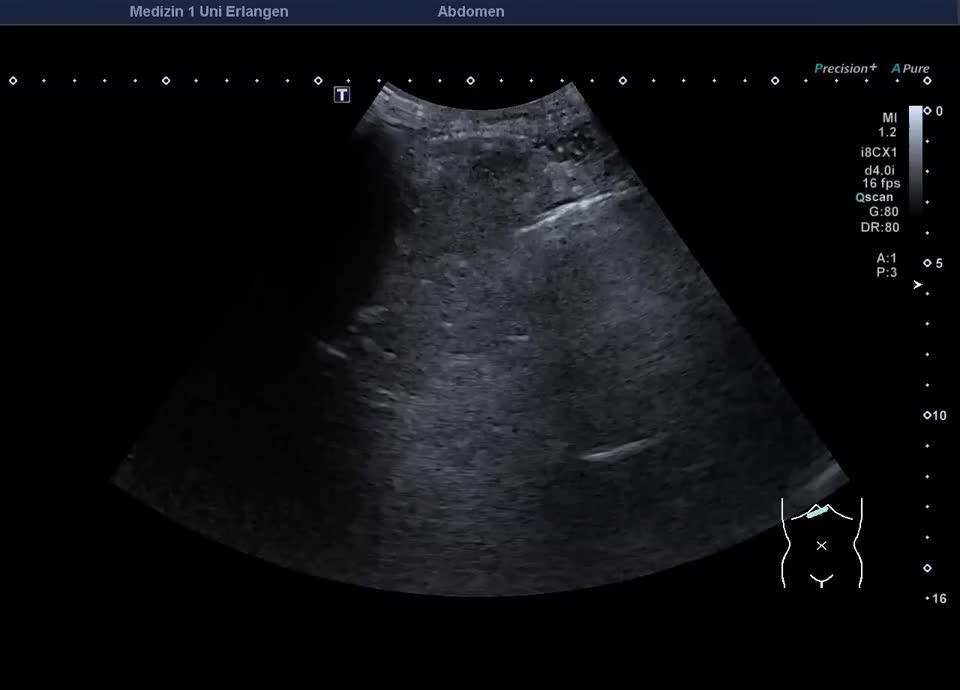

Umgehungskreisläufe im Milzhilus bei portaler Hypertension